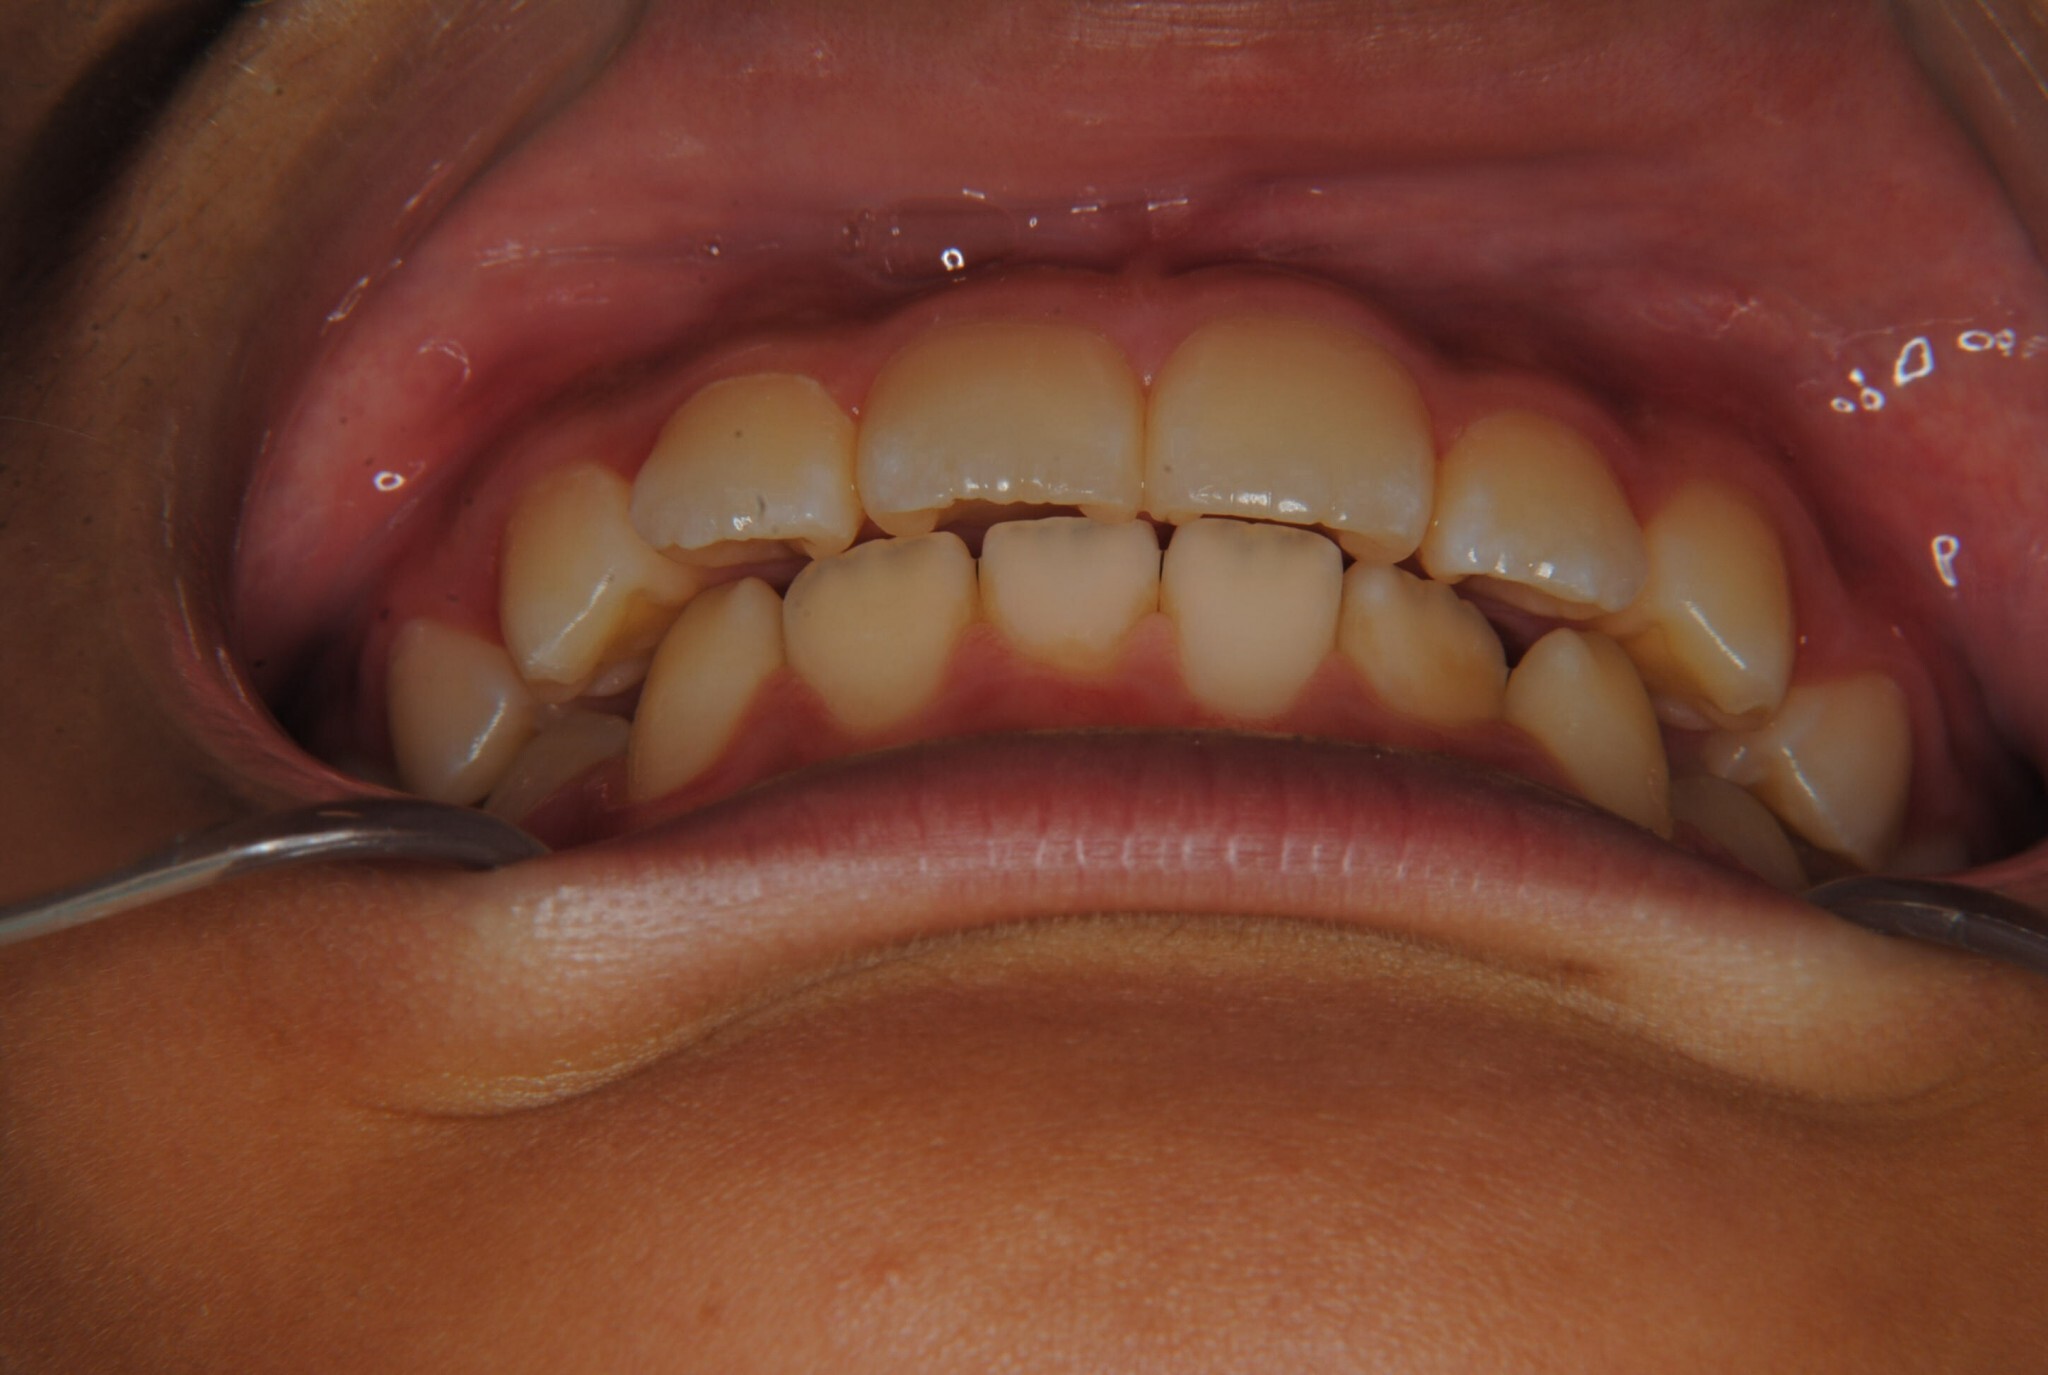

③年齢:初診時(左写真)8歳6か月、終了時(右写真)11歳4か月

⑧リスクと副作用:特に大きなリスクや副作用はありませんでした。拡大床装着直後は違和感があったようですが、特に痛みを感じることなく6.5mmまで拡大できました。その後永久歯への生え変わりも順調で、ほぼ正常な咬み合わせになりました。この後11歳4か月まで観察し、7番目の奥歯である12歳臼歯がきちんと咬んだので終了となりました。